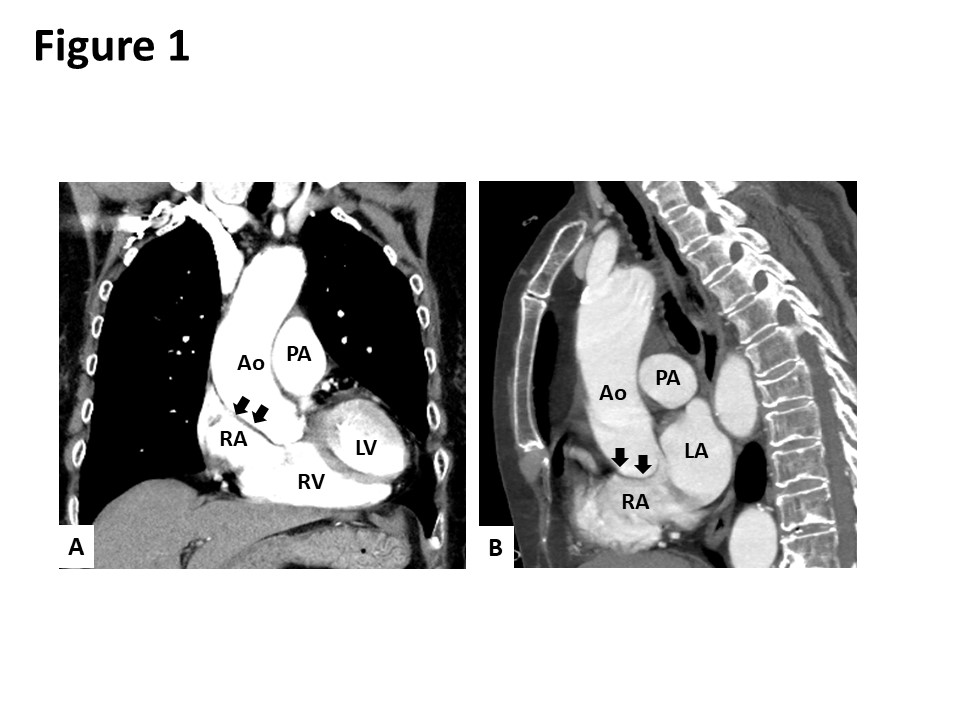

Case Presentation: An 80-year-old Japanese woman presented to our hospital with dyspnea in the sitting and standing positions. Two months prior to her admission, she had presented to another hospital with multiple vertebral compression fractures. After being discharged from the hospital, she developed dyspnea in the sitting and standing positions. She also reported an episode of syncope. Although the patient’s oxygen saturation on room air was 98% in the supine position, it declined to 83% in the sitting position and dropped further to 65% in the standing position. Contrast-enhanced computed tomography revealed the elongation of the aorta, which was compressing the right atrium and distorting the position of her heart (Figure 1). A transesophageal echocardiogram showed an oval-shaped secundum atrial septal defect (ASD) measuring 14 mm x 7 mm in size with a deficient aortic rim (Figure 2). The surgical closure of the ASD was performed. Following surgery, her oxygen saturation in the sitting and standing positions recovered to 98% on room air. She was discharged on the 23rd day after the surgery without any complaints of platypnea.

Discussion: Platypnea-orthodeoxia syndrome (POS) is a rare syndrome characterized by dyspnea and hypoxia when a patient is sitting or standing. The most common anatomical cause of POS is a right-to-left (RL) shunt through interatrial communications, including an atrial septal defect (ASD) or patent foramen ovale (PFO). In our case, based on the patient’s clinical course, her multiple vertebral compression fractures were suspected to have triggered the exacerbation of the RL shunting. To the best of our knowledge, only three cases of POS induced by vertebral fractures have been reported. A possible etiological mechanism to explain the induction of POS by vertebral fractures is as follows: the multiple vertebral compression fractures caused kyphosis and the subsequent distortion of the aorta resulting in right atrial compression and increased RL flow through the ASD.